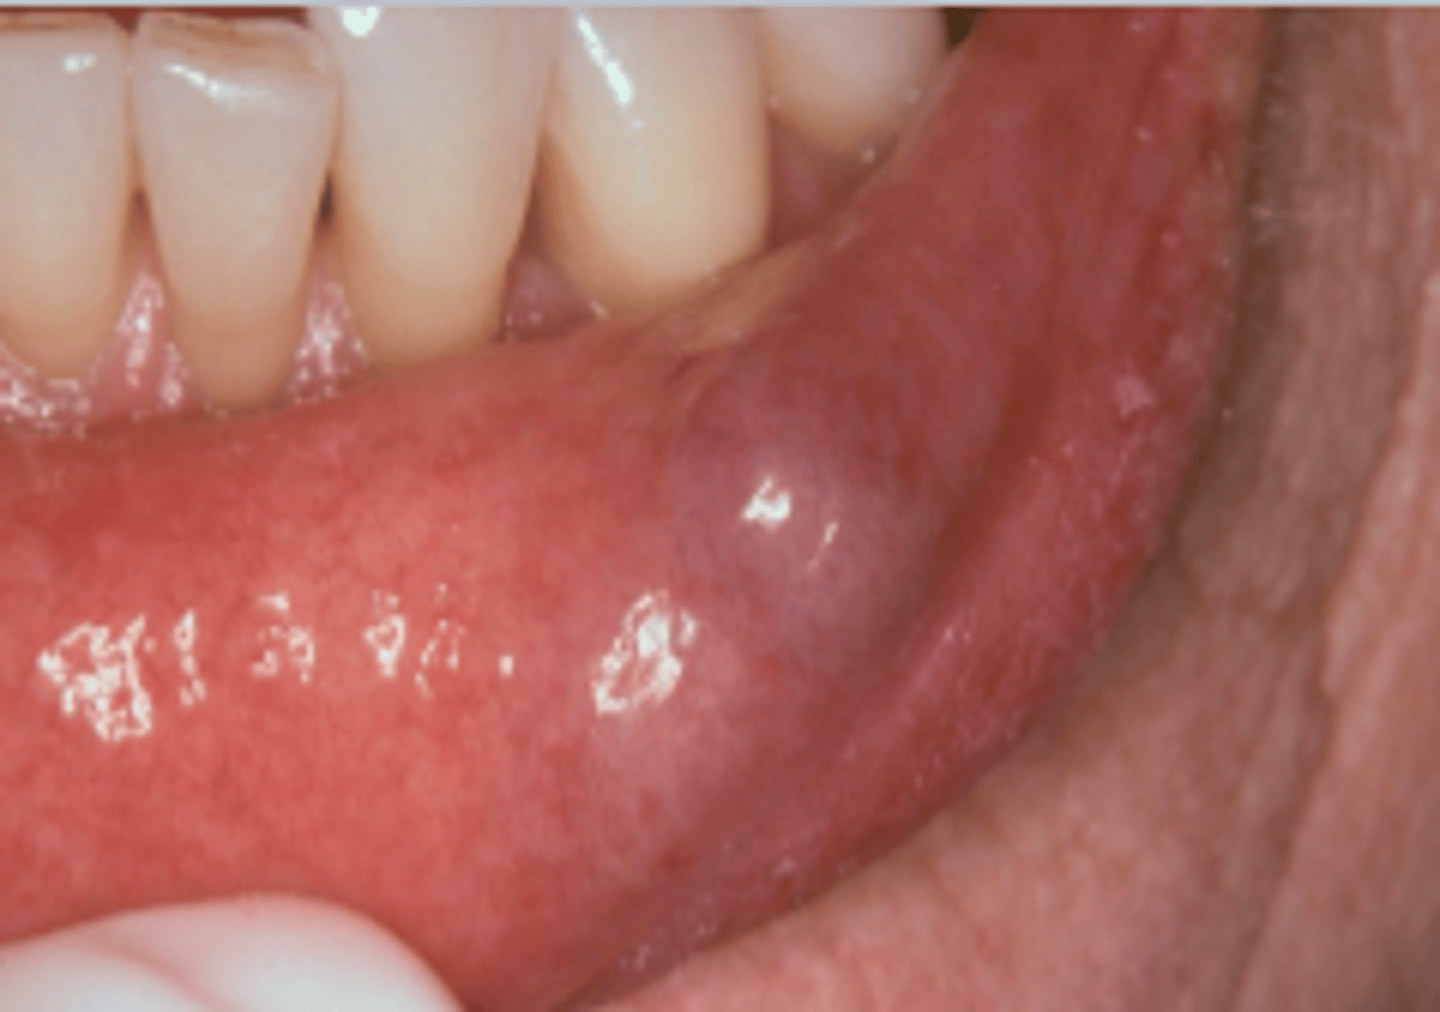

ID the pathology:

Mucocele

- Dome-shaped fluctuant vesicle

- Blue or mucosa-colored

- Most common on lower lip

- - May be seen anywhere w/ salivary glands